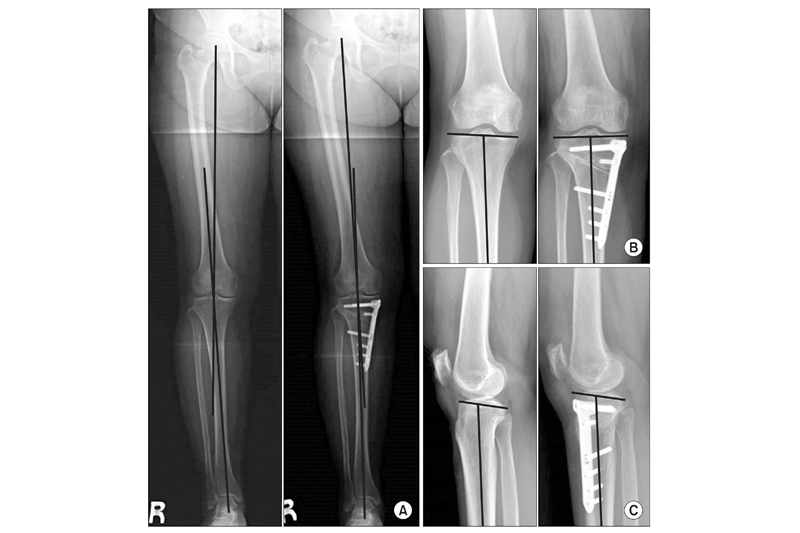

高位脛骨截骨術的原理是,於小腿脛骨上方切開缺口後,將脛骨微曲及固定後,按力學原則將膝關節的受力角度轉向往外側,以減輕內側受力引起的痛楚,保護內側已有損磨的軟骨,當中會植入物料作固定及輔助脛骨復原。由於手術複雜度較低,約歷時1至2小時即可完成。患者於術後4至6星期已可復康,得以減少疼痛及減慢關節磨蝕,手術效果大約維持10年。楊仕俊醫生解釋,由於高位脛骨截骨術只可改變膝關節受力情況,對整體膝結構沒有改變,所以要挑選勞損未算太差的患者。

(圖片來自Offical Journal of Korean Knee Society)